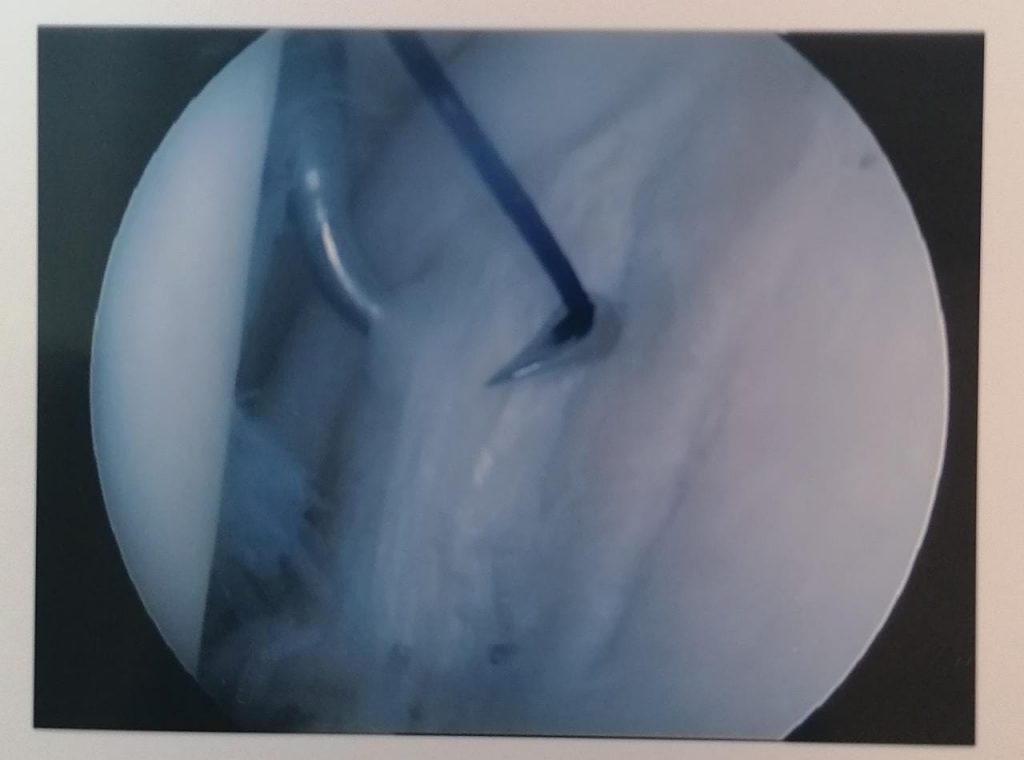

One common problem is a tear of the capsule where it adheres to the shoulderblade part of the joint. This is called a Bankart lesion and can be to the front or the back of the joint. Repair is done arthroscopically using anchors. The outcome of this method is usually very good. Recovery takes about six weeks with the physio being continuously involved.

Above are pictures showing the placement of a suture through the edge of the capsule (labrum) to the placement of the anchor as well as the end result. All of this happens through two small incisions.